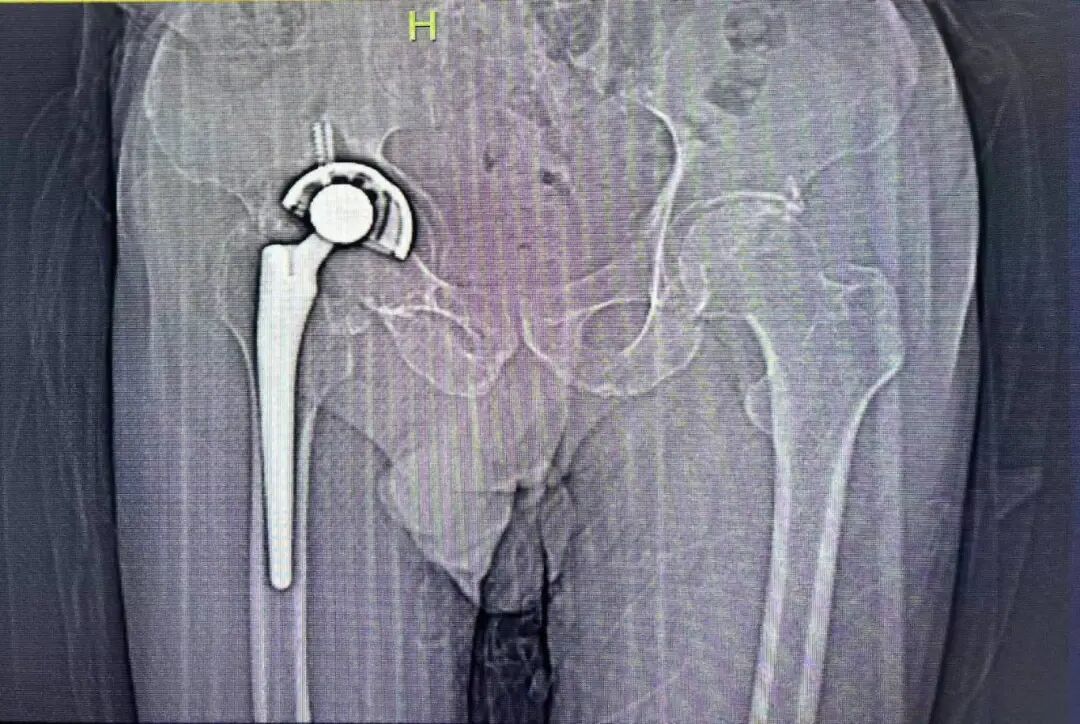

近日,由浙江大学医学院附属第一医院雷鹏飞教授团队顺利完成浙江首台VTS可视化智能辅助系统配合爱康HDR翻修系统+个性化定制3D打印多孔金属补块的复杂翻修手术。术中使用72毫米直径髋臼杯,结合3D打印个性化定制翻修补块,在VTS系统辅助下精准放置于规划位置,成功修复髋臼巨大骨缺损。

术后雷鹏飞教授表示,VTS系统与HDR系统首次搭档获得了良好的术后效果,VTS系统的引入让复杂手术简单化,术前规划让手术更安全,术中辅助指引让手术更精准。HDR定制外杯采用非组配设计,假体整体为EBM技术3D打印多孔结构,具有较高的粗糙度和摩擦系数。由于无需设计与内衬的连接结构,因此螺钉孔的布置更加灵活,为俗称的“满天星”设计,便于在残留的宿主骨上进行螺钉固定,实现牢靠的初始稳定性。